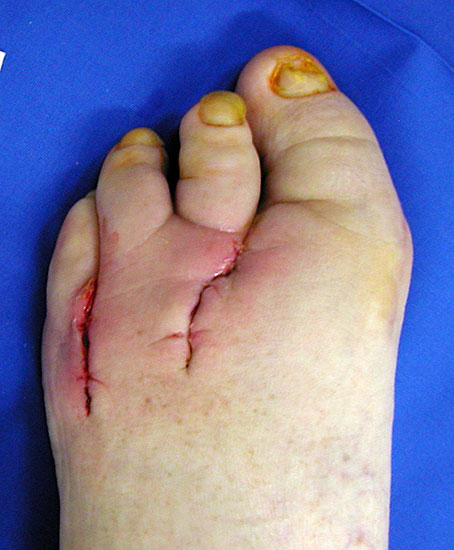

Eitrig-infiziertes Ulkus an der Spitze der 2. Zehe als Indikation zur Endgliedamputation.

Abbildung 13

Chronisches Ulkus mit Infektion (Abb. 13).